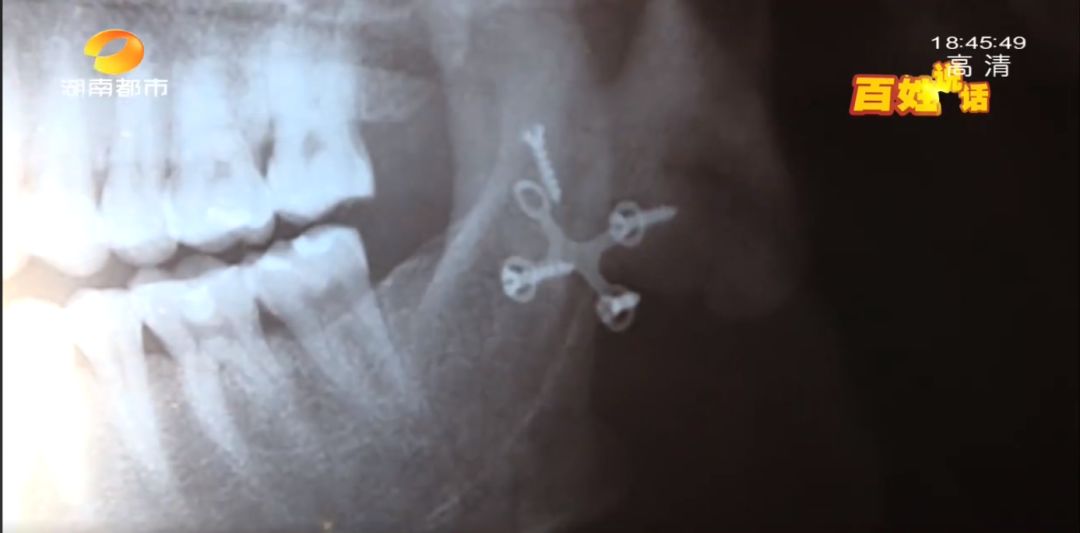

就在長沙“愛芮思”醫(yī)美機構(gòu)采訪時,記者見到了來自遼寧的張先生,幾乎是同一時期,他在這里接受了輪廓三項的整形,在進行術(shù)后復查時發(fā)現(xiàn),不僅下頜骨缺了一塊骨頭,就連連接骨頭的鈦釘螺釘也脫落了一顆,直到雙方協(xié)商解決方案時,張先生才知道,這家機構(gòu)并不具備磨骨等手術(shù)資質(zhì)。

張先生:我在我們當?shù)嘏钠影l(fā)現(xiàn),骨頭這里的釘子,一共是四顆釘子,有一顆釘子脫落了,然后我這個地方是,不該截的骨頭給我截掉了。

張先生:釘子現(xiàn)在還在我臉上,我沒動,還在我的臉里面。即使下頜骨現(xiàn)在有點形狀,是給我磨掉了,然后他也給我磨出問題了,就是我現(xiàn)在花多少錢也改變不了的。